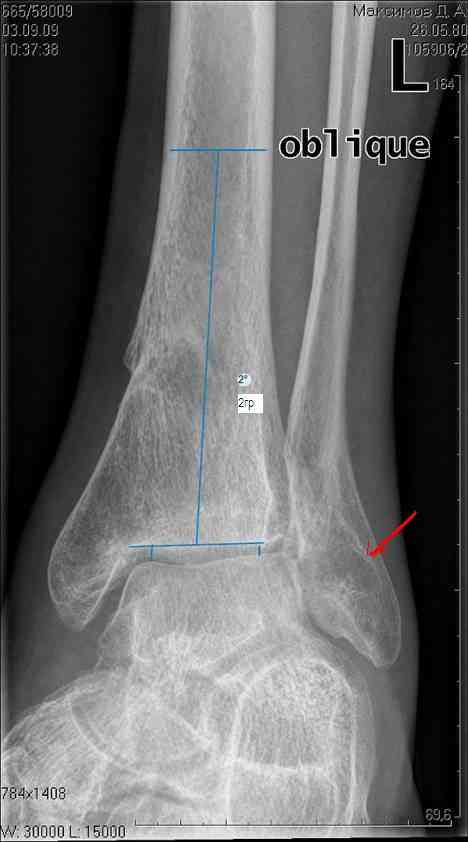

Здравствуйте коллеги. Представляю молодого человека 28 лет, получившего травму в апреле 2008года. Травму он получил на работе, левая голень со стопой оказались зажатыми между двумя тяжелыми предметами. В результате открытые переломы 1,2,3 плюсневых костей с размозжением мягких тканей над ними, открытый перелом наружной лодыжки со смещением дистального отломка кзади и подвывихом стопы кнаружи с размозжением мягких тканей над лодыжкой, закрытые переломы внутренней лодыжки и дистального метэпифиза большеберцовой кости.Учитывая наличие размозжения тканей стопы и области голеностопного сустава лечили в аппарате внешней фиксации. Переломы срослись, однако имеет место незначительный подвывих стопы кнаруже и неправильно сросшийся отломок наржной лодыжки (смещен кзади)Сегодня пациента ничего не беспокоит (с его слов. Клинически левый голеностопный сустав не отечный,пальпация всех структур данного сустава безболезненна. Имеет место ограничение тыльного сгибания стопы (сгибание к тылу стопы составляет до 10-15 гр), в связи с этим имеет место гиперподвижность в суставе Шопара. Пациент ходит со стельками (индивидуальные).Нужна ли пациенту реконструктивная операция в голеностопном суставе: исправление взаимоотношений в наружных отделах голеностопного сустава или что еще?С уважением Батал Шушания.

Наверное наружная лодыжка ушла назад не одна - такое впечатление, что был сломан и задний отдел б/берцовой кости (малоберцовая вроде прямая, а эпифиз широковат, как-то). Поэтому, думается, что гоняться за лодыжкой и синдесмозом не стоит. А вот вальгусный голеностоп и деф. артроз таранно-ладьевидного сустава - налицо. Вальгус надо устранять и, скорее всего, в АВФ единым блоком (надлодыжечная остеотомия обеих костей). Что пациент сам-то хочет? Если его устраивает нынешнее положение вещей, в стельках ему комфортно, то зачем огород городить (к этому суставу, рано или поздно, все-равно придется возвращаться)?

На рентгенограмме вальгус, на боковом снимке не видна суставная щель и клинически явная деформация.